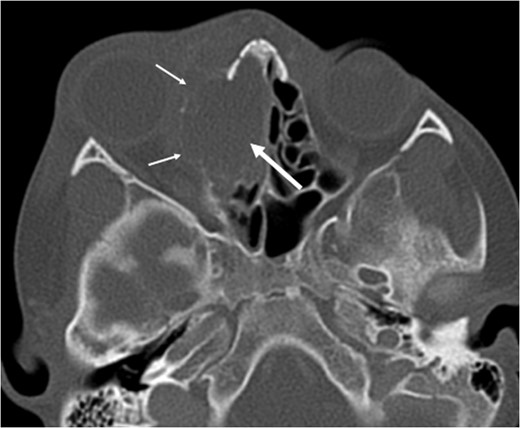

A 6-year-old boy with a background of asthma presented to a tertiary paediatric unit in May 2016 with a 3-day history of right eye pain, proptosis and erythema under the care of the ENT team. A provisional diagnosis of a periorbital cellulitis was made secondary to ethmoid sinusitis and management with intravenous antibiotics (ceftriaxone), intranasal steroids, saline douches and topical oxyxlometazoline was initiated. Ophthalmological assessment demonstrated normal colour vision, acuity and light reflexes bilaterally but also proptosis-related ophthalmoplegia. Computed tomography (CT) imaging of the orbits and paranasal sinuses demonstrated complete opacification of the right-sided paranasal sinuses and compromise of the right frontal and ostiomeatal unit. In addition there was an expansile abnormality centred on the ethmoidal labyrinth with bony remodelling of the lamina papyracea and a subperiosteal collection adjacent to the medial orbital wall (Figs 1 and 2). The most likely diagnosis was felt to be an infective process with mucopyocele formation complicated by a subperisoteal post-septal collection. An MRI scan with gadolinium of the orbits and sinuses confirmed the unilateral pattern of sinus opacification within the right frontal, ethmoids and maxillary sinus. The lesion demonstrated multiple fluid–fluid levels and peripheral enhancement (Figs 3 and 4). The patient was treated by endoscopic drainage of the lesion, which revealed only blood. He initially had some improvement of his proptosis but recurred within a few days and so further, more extensive endoscopic debridement was performed.

Axial T1 post-contrast sequence with fat suppression demonstrating peripheral enhancement (white arrows) but no internal or solid enhancing components to suggest that this is a secondary ABC.

At this point the MRI was reviewed and the possibility of an ABC was raised. This was due to the presence of fluid–fluid levels, cyst within a cyst appearance and lack of restricted diffusion within the sinonasal contents and material drained at the time of the first endoscopic procedure. He was discharged home on oral co-amoxiclav, and topical betamethasone nose drops.